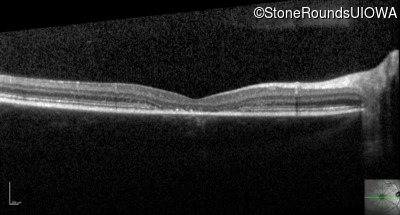

Optical Coherence Tomography - Right - 20/100 -1

Exemplar / OCT Stack

OCT Stack